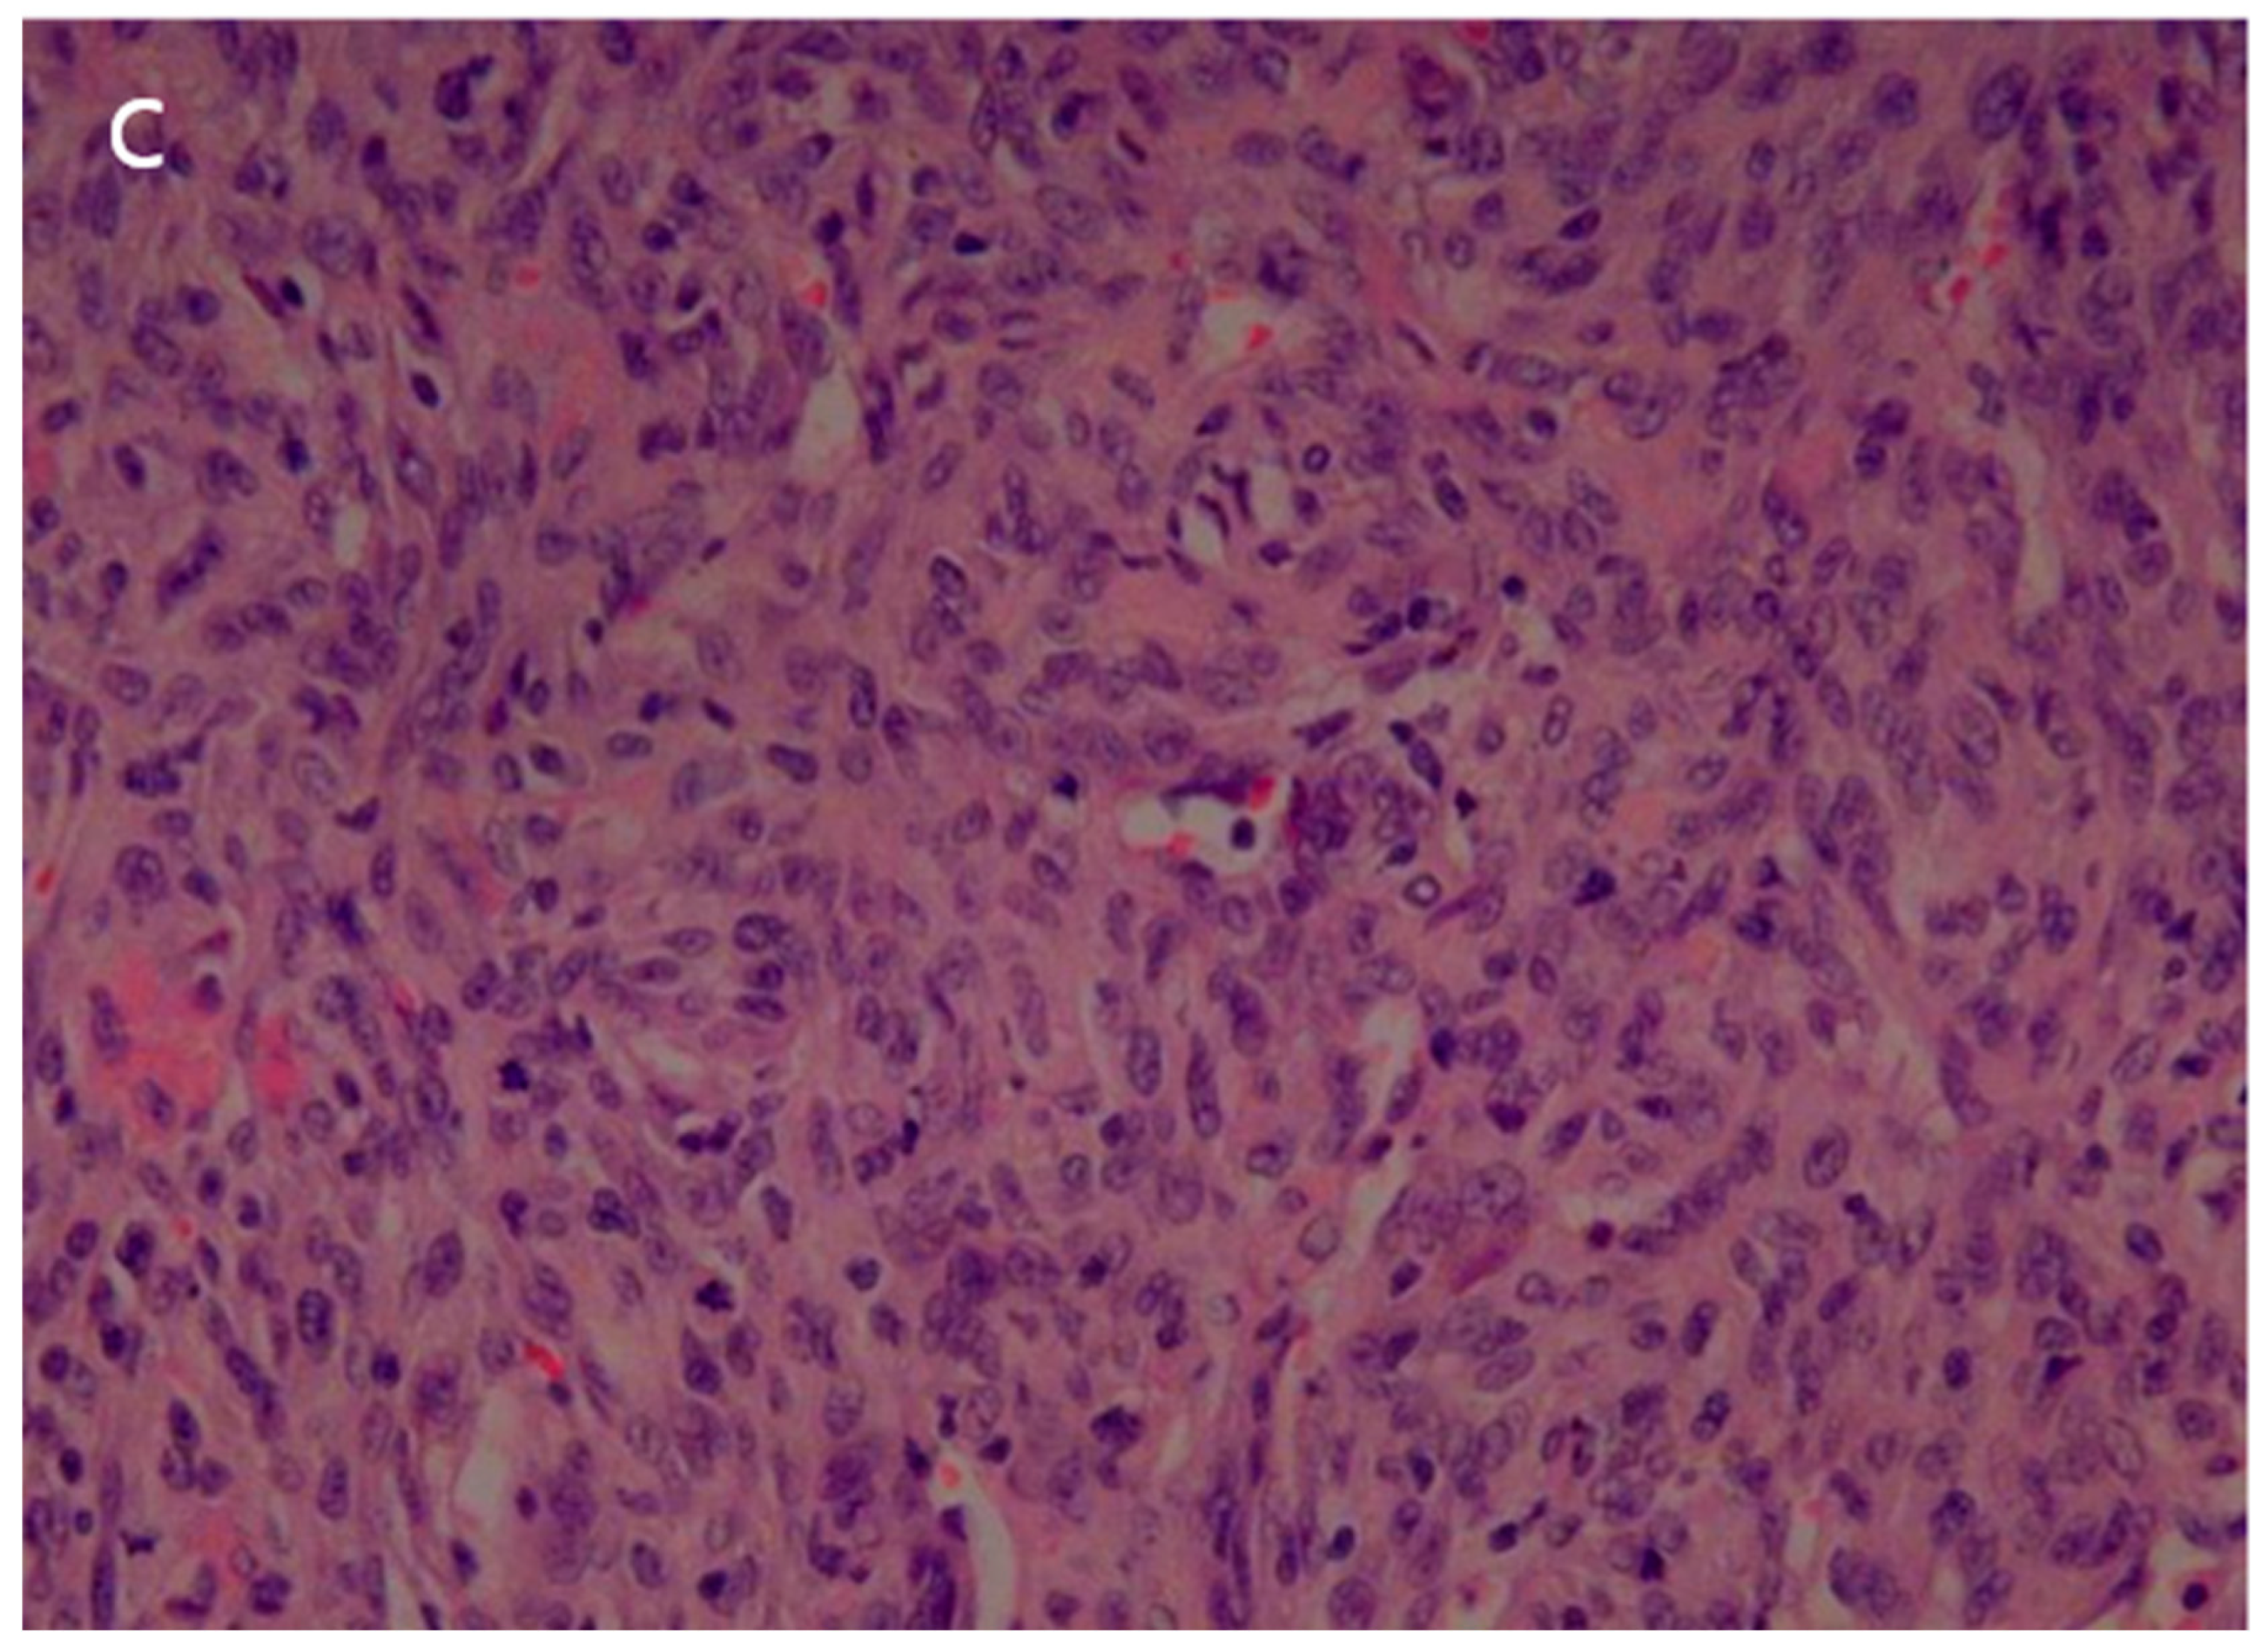

Figure 5.

(a) The surgical specimen revealed a well-circumscribed, pale-yellow, soft mass (5.5 cm in diameter) with hemorrhage. (b) Microscopic imaging of the tumor showed a hemangiopericytic pattern and areas of coagulation necrosis (hematoxylin and eosin [HE] × 100). (c) Numerous mitotic figures and marked nuclear pleomorphism were observed in high-grade areas (HE × 400).

The patient underwent a right upper lobe lobectomy. Gross examination showed a well-circumscribed, pale yellow, soft tumor with hemorrhage, measuring 5.5 × 5.0 cm (Figure 5a). Histopathological analysis revealed a hemangiopericytic growth pattern with areas of coagulation necrosis (Figure 5b). Numerous mitotic figures and marked nuclear pleomorphisms resembled high-grade pleomorphic sarcomas (Figure 5c). Immunohistochemically, the tumor cells were focally positive for CD34 and negative for epithelial markers, such as cytokeratin and EMA (epithelial membrane antigen). Neoplastic cells were negative for desmin, myoglobin, Bcl-2, calretinin, and HMB-45. The immunohistochemical results favored the diagnosis of a malignant solitary fibrous tumor.